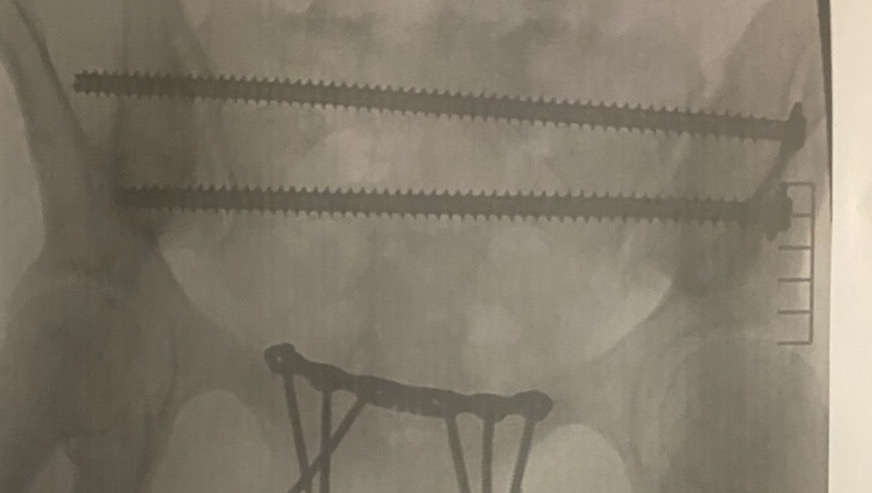

She broke her pelvis, fractured her back, lacerated her kidney, suffered a concussion as well as nerve damage that has left her with unimaginable pain. She spent 10 days in the hospital and underwent a 9 hr surgery to repair her pelvis. Not to mention the recovery that is to come as she will need to learn to re-walk.

Currently she is non weight bearing on one leg due to the severity of the pelvis break. It was determined this would be the case for about 3 months. She has been away from her four beautiful boys and husband for many nights staying with family due to the amount of stairs in her home. She is so grateful for the help she’s received thus far.